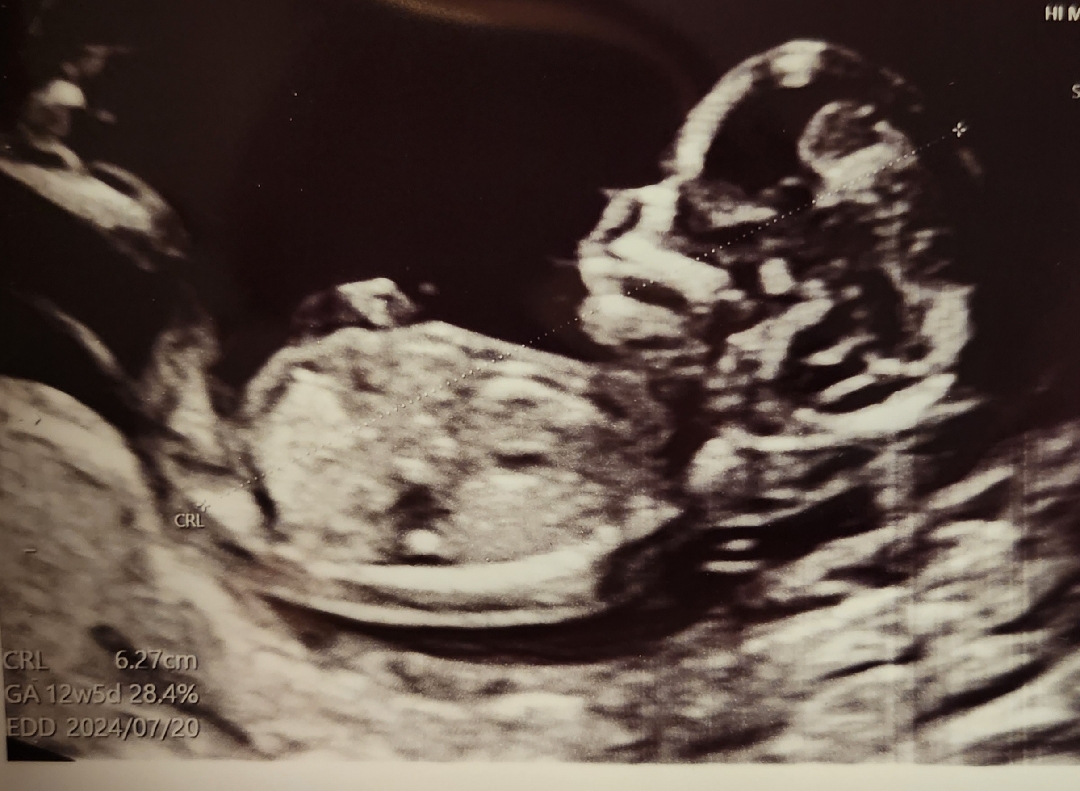

12주차에 병원 다녀와서 성별이 궁금하네용! 보실 수 있는분 의견좀 부탁드려요 ㅎㅎ

사진에 생식기 부분이 안보이네요 보이는 사진으로 판단하셔야 할 것 같아요!